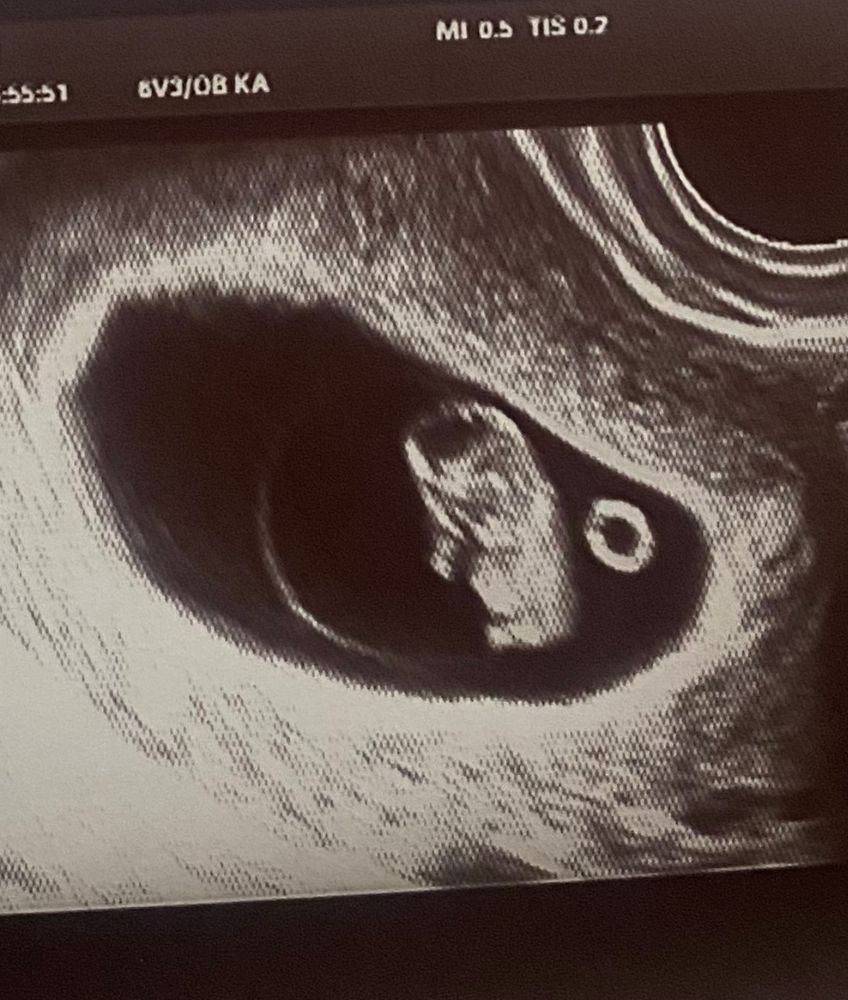

Томительное ожидание , узи 8+2

По итогу я уже увидела прям маленького человечка , а не козюльку )))) даже не ожидала что так быстро растёт ) почти догнал свой срок 🥹в общем выдохнула … и решила уже в жк может пойти … ктр 17,5

Ой, ну прям упитанный человечек, вполне себе довольный жизнью. Даже подкова справа на счастье))) Отличное КТР и все будет хорошо, поздравляю, и легких вам месяцев впереди...